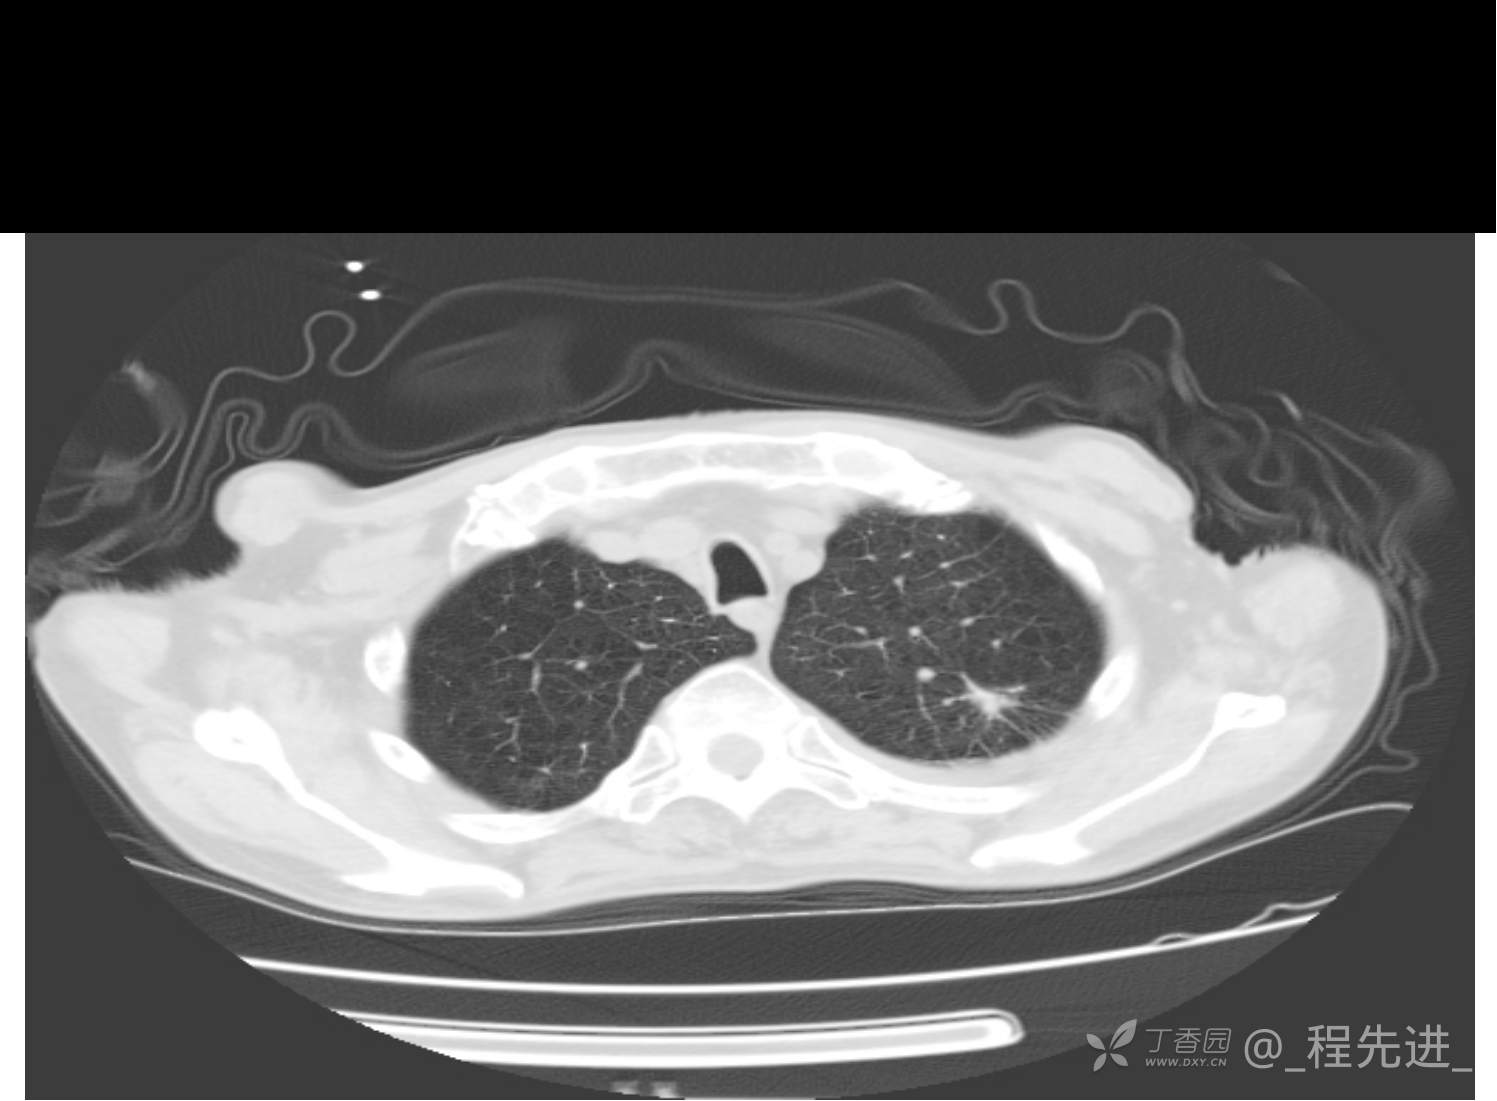

患者性别:男

患者年龄:81岁

简要病史:反复咳嗽、咳痰20余年,加重1周。两肺呼吸音低,可闻及散在干湿啰音。